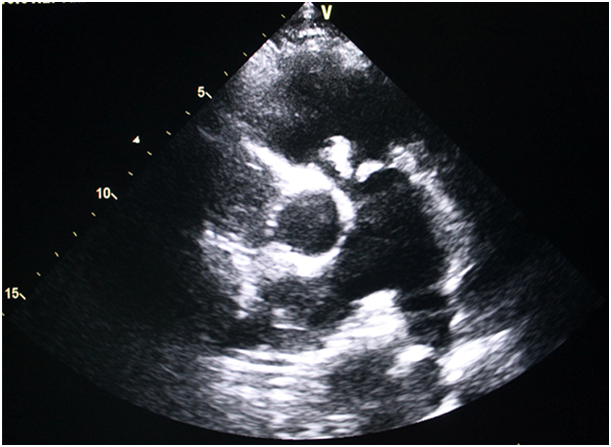

30year male patient was admitted with history of fever and occasional cough for 5months. He was treated in a local hospital for the same with oral and intravenous antibiotics several times but that led to transient symptomatic improvement. On physical examination his axillary temperature was 99degree F, chest was bilaterally clear and cardiovascular system examination revealed loud S2 with fixed split and ejection systolic murmer in pulmonary area. Routine blood test revealed total count 20000/cmm, 71% neutrophil, ESR 91mm,CRP was positive (titre>0.6mg/dl). Liver function test and renal function test were eithin normal limit. Blood culture sent was sterile after 48hours and 7days aerobic/anaerobic incubaton. Chest x ray showed few cavitary lesion following which CT scan thorax was done that revealed multiple thin walled cavitary lesion suggestive of sequelae of old infection. 2D echocardiography showed OS-ASD of 18mm with left to right shunt and mobile vegetation was seen on pulmonary valve. Patient was started on intravenous ceftriaxone and gentamycin. Subsequent echocardiography during hospitalization showed only mild to moderate pulmonary regurgitation and moderate pulmonary hypertension along with the previous findings. The patient had no other clinical manifestation, or identifiable complication including thromboembolism. CRP was negative after completion of antibiotics. The patient was discharged after 6 weeks in stable condition. Nevertheless the pre discharge echocardiography revealed persistence of vegetation, which had developed a fibrotic appearance and persistent mild to moderate pulmonary regurgitation.

Right-sided infective endocarditis (RSIE) is a rare condition constituting 10% of cases of Infective Endocarditis.1 Infective endocarditis (IE) involves the aortic valve as the most common followed by the mitral valve as more common. Tricuspid and pulmonary valve are the least commonly involved. In patients with congenital heart defects, left, right and both sided IE accounts for 46.4%, 32.7% and 2.3%, respectively.2 Prevalence of isolated tricuspid and pulmonary valve IE is 2.5-3.1% and 2%, respectively.3,4 It is usually seen to be associated with intravenous illicit drug use (IVDU) or central catheter use. Staphylococcus aureus is the most common infectious agent in all cases.5 Most cases of right sided infective endocarditis involves the tricuspid valve. Incidence of RSIE is on the rise due to increase number of patients using central venous lines, as well as pacing and other intravascular devices.6 It is also commonly seen in patients on maintenance hemodialysis. Infective endocarditis involving the pulmonic valve is extremely rare, accounting for only 1.5 to 2.0% of hospital admissions for infective endocarditis.7 IE may be isolated to the pulmonic valve alone or it may concomitantly affect other valves. Both structurally normal and heart with abnormal valves have been associated with pulmonic valve endocarditis. Low incidence of infection on the pulmonic valve compared with other cardiac valves can be explained relating to differences in hemodynamic pressures across the valves, oxygen saturation, underlying congenital or acquired valvular abnormalities. The endothelial lining and relative vascularity of the valves has also significant role. Clinical manifestation of pulmonic valve endocarditis is similar to that of tricuspid valve infection. Fever, breathing difficulty, pleuritic chest pain are the predominant symptoms. Radiographic and laboratory evidence frequently corroborates the presence of pulmonary embolism. Approximately one half of patients will have pulmonic regurgitant murmur present on cardiovascular examination. Due of the nonspecificity of symptoms and lack of peripheral stigmas typically associated with mitral or aortic valve involvement, the diagnosis of pulmonic valve endocarditis usually takes time. It may be delayed for up to 6months. A high index of suspicion is needed to diagnose a case of pulmonary valve endocarditis for better management and outcome. Interatrial communication has been reported in some cases of RSIE, however, these involved normal native pulmonary valves.8 Pulmonary valve IE associated with ASD has rarely been reported in literature. To conclude, in presence of longstanding fever with non specific symptoms a proper assessment of pulmonary valve should be done with TTE and also TEE if possible. Other clinical conditions should be corroborated also specially in situations when a patient is having predisposing heart disease. A high clinical index of suspicion with proper diagnostic method will help in diagnosing and proper management (Figure 1) (Figure 2).

Figure 1 Transthoracic Echocardiography short axis view showing vegetations on pulmonary valves.